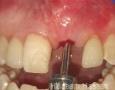

Pictures

Surgery